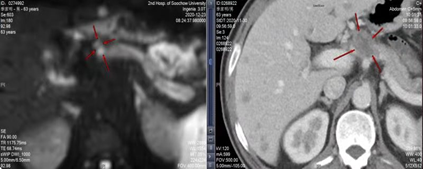

第二次复查发现,肝内多发异常信号灶、左侧肾上腺、胰颈部结节,较前片(CT:2020-11-30)病灶缩小。

2020-12-21(左)与2020-11-17(右)CT结果

2020-12-23(左)与2020-11-30(右)CT结果